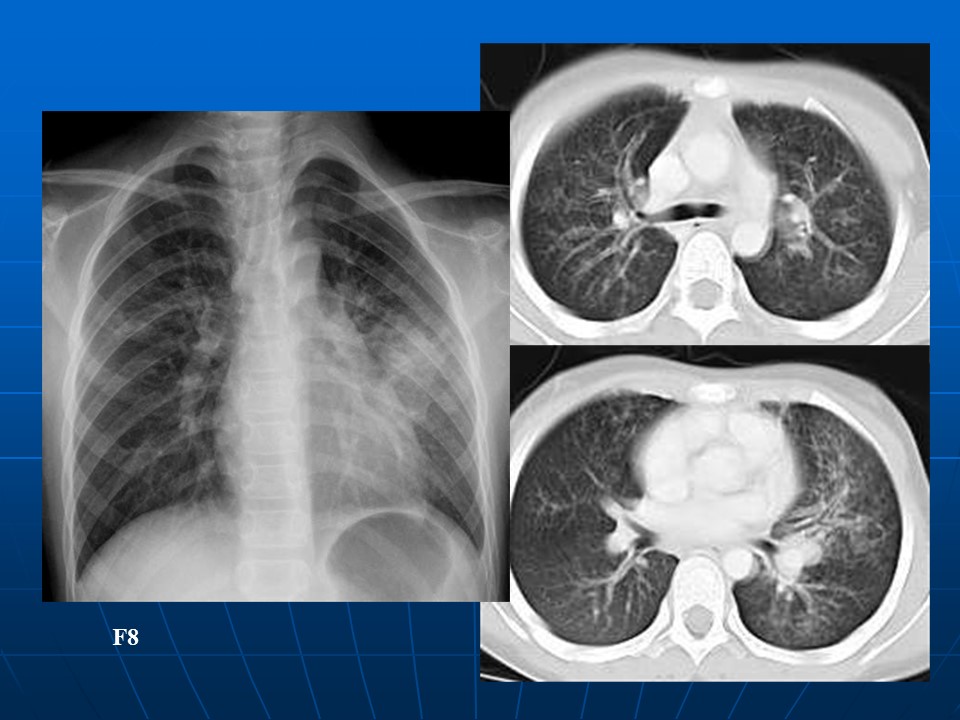

【病例】矽肺1例CT影像表现